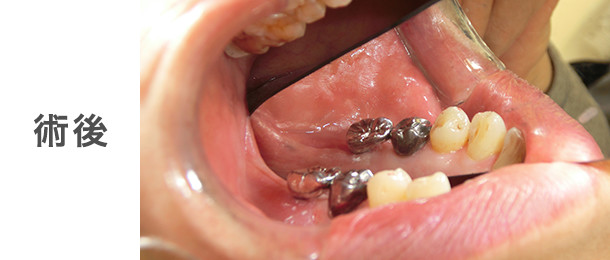

![]() |